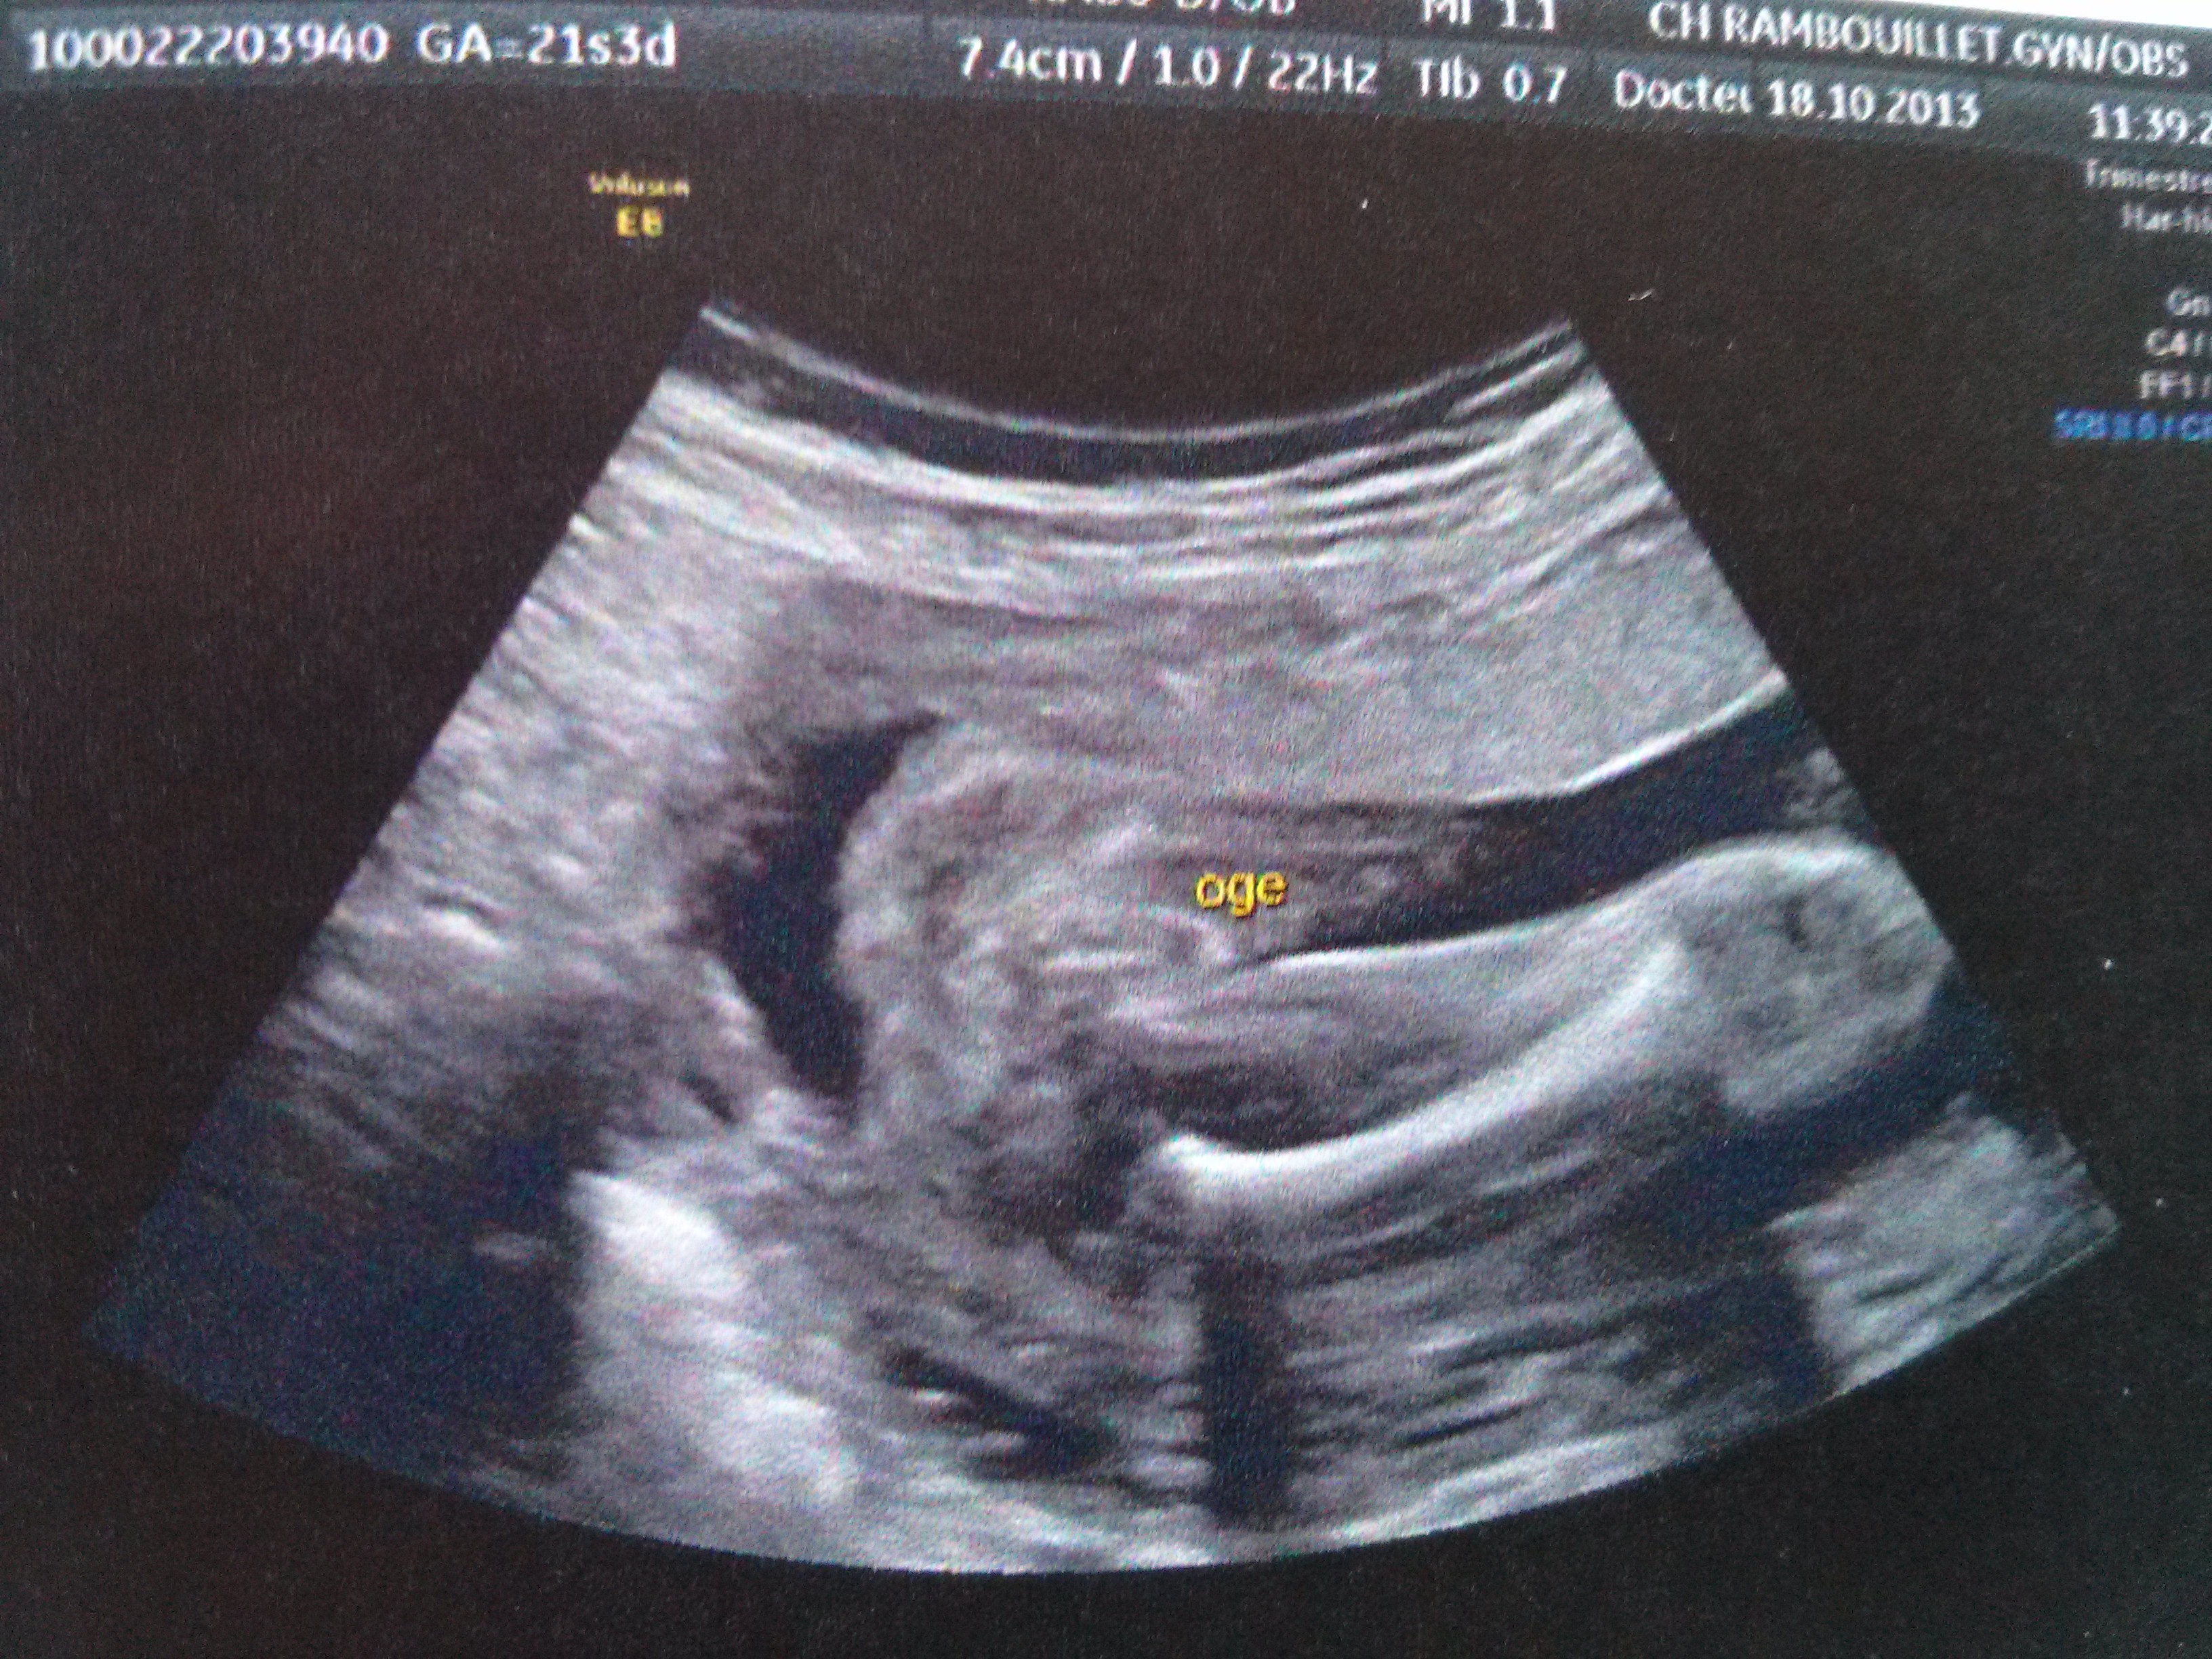

Shop BSA Fury 22 55mm 250 Domed Pellets Airgun Air Rifle Hunting Target 22 Free delivery and returns on all eligible ordersView the profiles of people named Lassa Bebe Join Facebook to connect with Lassa Bebe and others you may know Facebook gives people the power to shareCalendrier La 22ème semaine d'aménorrhée (22 SA) équivaut à semaines de grossesse Vous êtes dans votre 5ème mois de grossesse Bienvenue dans votre ème semaine de grossesse Votre bébé à semaines de grossesse / La maman à semaines de grossesse / To do liste

Delivery Options Be Unlimited £995 (Unlimited delivery for a year) UK Standard £350 UK Next Day Delivery £450 (Before 11pm SundayFriday & before 10pm Saturday) UK Nominated Day Delivery £450 (Before 11pm SundayFriday & before 10pm Saturday) Click & Collect £350 Free for orders over £40 on eligible products Otherwise standard delivery charges applies Côté maman C'est en principe entre la vingtième et la vingtdeuxième semaine de grossesse que s'effectue l'échographie morphologique C'est unLe fœtus est une personne qui une véritable vie intrautérine partir de 3 mois Il bouge des qu'il apparaît à la taille minuscule Il acquiert des battements cardiaques visibles à l'échographie à partir de 37 jours de sa conception et à 1415 sa il a déjà une vie avec des rêves De jour en jour ,le fœtus évolue ,augmente de taille et prend du poids l'évolution peut être

21 & 23 SAS are the Elite Army Reserve, and provide an opportunity for soldiers to work within a unique, diverse and exciting organisation which takes pride in its heritage, role and professionalism Service is physically and intellectually challenging, but the rewards are significant In addition to a strong sense of purpose in embracing the challenges of a complex world, 21 & 23 SAS provideView the profiles of people named Bebes Sasa Join Facebook to connect with Bebes Sasa and others you may know Facebook gives people the power to shareLe bébé à la SA 22 Pendant la semaine 22 d'aménorrhée le bébé mesure environ 28 centimètres des pieds à la tête, et pèse environ 475 grammes Son poids a beaucoup augmenté depuis la semaine dernière, ce qui est un indicateur de ce qui se passera à la prochaine étape

ème semaine de grossesse (22 SA) Lors de votre ème semaine de grossesse (22ème semaine d'aménorrhée), vous voilà parfaitement épanouie !Shop bebe's selection of fashion clothing and trendy clothes for women for every occasion Order the hottest styles and latest women's fashion from bebe, including stylish dresses, trendy jumpsuits, cute tops and more!The 22nd Armoured Brigade was an armoured brigade of the British Army that saw service during and after the Second World WarThe brigade was formed on the outbreak of war on 3 September 1939 from Territorial Army (TA) armoured regiments It saw a considerable amount of action during the war, beginning with the Western Desert Campaign where it was engaged in Operation